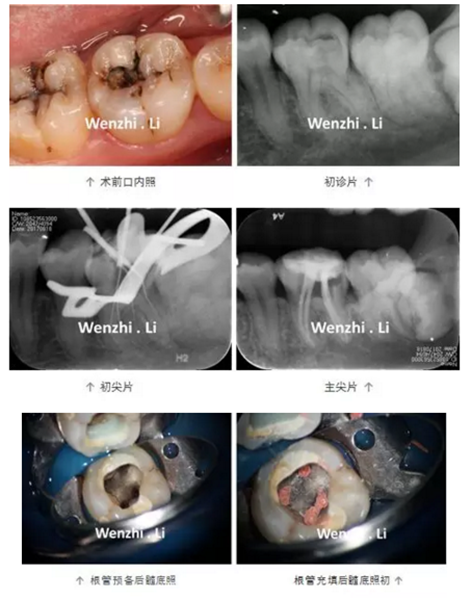

病例三 | 下頜第一磨牙彎曲根管一例

年輕女性患者因左下后牙間斷性自發(fā)性疼痛及冷熱刺激痛1個(gè)月就診,診斷為36慢性牙髓炎。局麻下,橡皮樟隔離下去腐,開髓,揭頂,可見髓腔鈣化,顯微鏡下超聲去除鈣化物,探及4個(gè)根管口,拍攝初尖銼片顯示MB根管為重度彎曲根管、DL根管彎曲極近根尖區(qū),X線片上未顯示。17% EDTA配合PathFile、Protaper NEXT 鎳鈦器械預(yù)備根管,實(shí)現(xiàn)連續(xù)錐度的根管形態(tài),5.25% NaClO沖洗,連續(xù)波熱牙膠根管充填4個(gè)根管,拍攝根充片,X線片顯示根充恰填。隔濕干燥,自酸蝕粘接,SDR+納米樹脂充填。

1.下頜第一磨牙解剖形態(tài);84%的下頜第一磨牙根管為彎曲根管,大 多數(shù)的下頜第一磨牙為DL根管彎曲,且彎曲程度不一。DL根管通常向遠(yuǎn)中頰側(cè)彎曲彎曲根管預(yù)備并發(fā)癥;

2. 預(yù)備彎曲根管技巧:器械預(yù)彎,建立直線通路;使用柔韌性及抗疲勞強(qiáng)度更好的鎳鈦旋轉(zhuǎn)器械;足量及有效的超聲根管蕩洗;連續(xù)波加壓充填技術(shù)。PathFile柔韌性好,在足量根管潤(rùn)滑劑下,可以順暢的通過根管彎曲部。Protaper NEXT 具有較好的柔韌性及抗疲勞強(qiáng)度,可降低預(yù)備彎曲根管時(shí)出現(xiàn)根管偏移的風(fēng)險(xiǎn)。